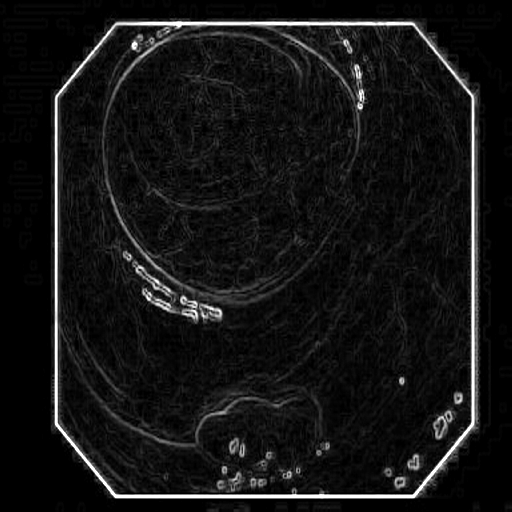

3.3 Edge-Guided Feature Enrichment Unit

The scarcity of annotated data in clinical practice hinders existing methods’ ability to capture polyp boundaries accurately. To address this, we propose the Edge-Guided Feature Enrichment (EGFE) unit, designed to enhance boundary quality in segmentation masks. EGFE robustly preserves edge information, mitigating the issue of weak boundaries, bridges the semantic gap between low-level and high-level features, and directly captures spatial features of polyps from input images. A pre-processing step incorporating a 2D Sobel operator [32] ensures the preservation of crucial edge details during convolutions.

The Edge-Guided Feature Enrichment (EGFE) unit actively enhances feature representation by integrating edge knowledge into the set of features. It applies a Sobel operator to the input feature set, generating separate gradient magnitude maps for horizontal and vertical directions (Fig. 3). As illustrated in Fig. 3, the Sobel operation in a single direction captures limited information about the polyp. However, combining these maps (Fig. 3(d) and Fig. 3(h)) effectively captures polyp boundaries and enriches learned features. The final gradient magnitude map, produced using the Euclidean norm (Eq. 1), highlights regions with significant intensity changes at polyp boundaries.

where , , and denotes 2D Sobel operation, ReLU activation function, the number of 2D convolutions with respectively, and represents the edge-guided features learned at the -th layer. This element-wise addition facilitates the fusion of edge information extracted by the Sobel operator with the spatial features learned by the convolutional layers. This fusion enables the framework to focus on and refine the representation of polyps, ultimately contributing to enhanced segmentation performance.